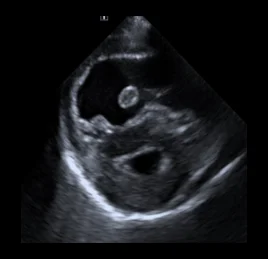

• 퇴행성 판막질환

• 동맥관 개존증 - PDA

• 폐동맥고혈압